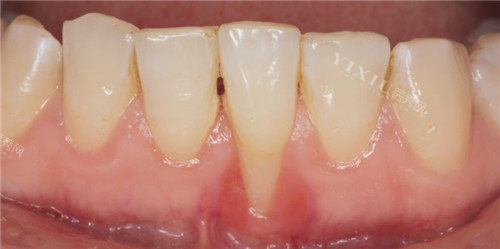

近段日子,我饱受牙龈萎缩的困扰。一开始,只是刷牙时偶尔出血,我没太在意,觉得可能是上火或者刷牙太用力了。可后来,牙龈越来越红肿,牙齿也开始隐隐作痛,甚至牙根都露出来了,不仅影响美观,还让我吃东西变得小心翼翼,生怕碰到敏感的牙根。我意识到,这可不是小问题,必须得去看医生了。

在治疗牙周病的这段时间里,我每天都盼着牙龈能快点好起来。每次照镜子,看到红肿的牙龈,心里就充满了焦虑。不过,随着时间的推移,我发现牙龈出血的情况逐渐减少了,红肿也慢慢消退了,这让我看到了一丝希望。